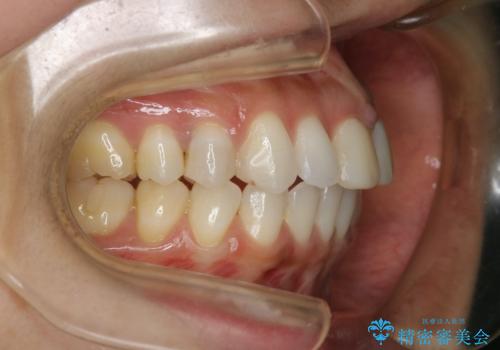

すきっ歯を治したい。インビザライン・ライトによる矯正治療

- 正中離開を気にされて来院された患者様です。

インビザラインでの治療を希望され、正中離開のみ治したいとのことだったので、インビザライン・ライト(片顎)での治療を選択しました。